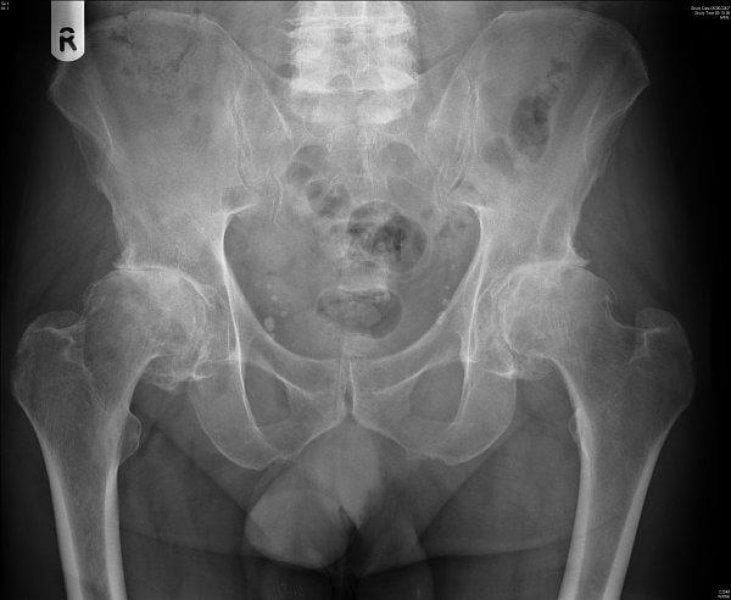

Тазобедренного сустава

Заболевание развивается на фоне коксартроза. Из-за истончения хрящевой прослойки головка бедренной кости перестает плавно смещаться при ходьбе.

Нередко от нее отщепляются небольшие участки, которые начинают свободно перемещаться в полости сустава. Если они попадают между костными поверхностями, то их «заклинивает». Возникает «суставная мышь», проявляющаяся в полном или частичном ограничении движений.

- При артрозо-артрите тазобедренного сустава из-за повышенных нагрузок быстро истончается хрящевая ткань. Вследствие сужения суставной щели растут остеофиты, часто появляются кисты. Поэтому снижается опорная функция ноги, возникают боли при любом движении.

Особенно тяжело переносится артрозо-артрит тазобедренного сустава, так как боли сильно ограничивают движение